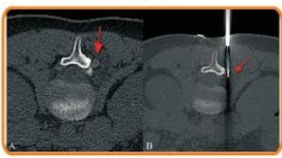

Once the region is anaesthetised, the radiologist will introduce the biopsy needle by means of a small incision. The stereotactic biopsy procedure needs computer guidance to allow the insertion of the needle to accurately position where desired. The method can also be applied using a vacuum-assisted device that can help in acquiring several tissue samples through one single incision in minimal time.

Tissue samples will be collected from most patients, but a small marker might be placed inside the breast, close to the biopsy site, to be able to find the area later. This can take 30 to 60 minutes. And then you will be observed for a little while, and you’ll be allowed to go back home.